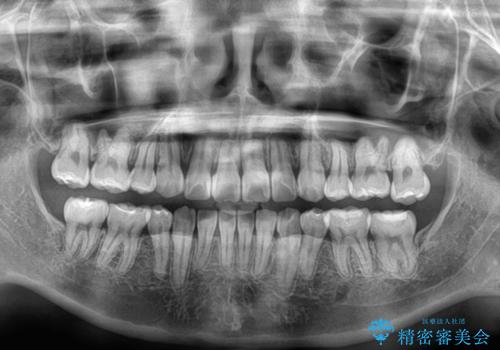

転位歯や埋伏歯などの難易度の高い抜歯矯正治療

重度叢生のため、大臼歯をしっかりと咬合させるために、下顎は左右第二小臼歯を、上顎は前歯部の叢生を解消するために左右第一小臼歯を抜歯し、口元の突出感を改善するために、上顎大臼歯が前方に移動しないようにするために、補助装置による架強固定を行うこととしました。

叢生は思ったよりも早期に改善されましたが、舌の突出癖による上下前歯の非接触が全く改善されず、2年間ほど治療期間が延びる結果となってしまいました。